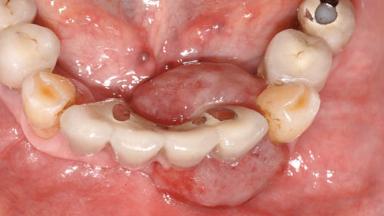

Peripheral Giant-cell Granuloma Associated with Peri-implant Tissues

# of Teeth 10

# of Implants 5